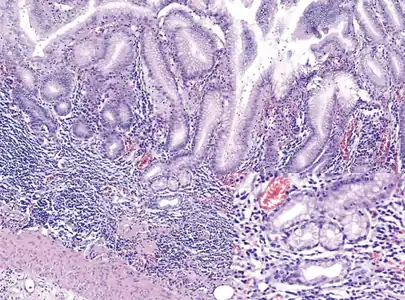

Atrophic gastritis under low power. H&E stain.

Autoimmune metaplastic atrophic gastritis (AMAG) is an inherited form of atrophic gastritis characterized by an immune response directed toward parietal cells and intrinsic factor.[6] The presence of serum antibodies to parietal cells and to intrinsic factor are characteristic findings. The autoimmune response subsequently leads to the destruction of parietal cells, which leads to profound Achlorhydria (and elevated gastrin levels). The inadequate production of intrinsic factor also leads to vitamin B12 malabsorption and pernicious anemia. AMAG is typically confined to the gastric body and fundus.